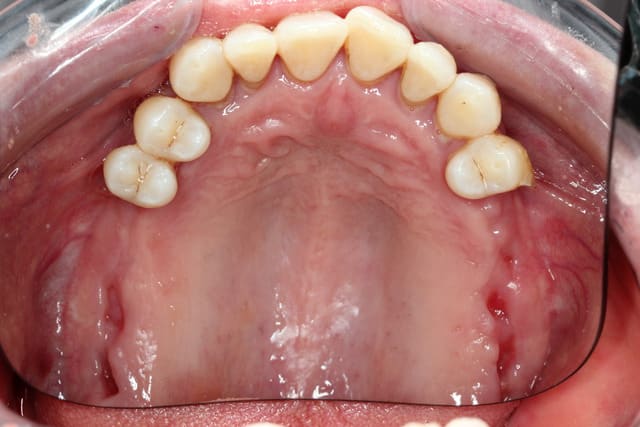

1.Bon... situation pré-extractionelle ( Je crois qu il faillait vraiment extraire )

2. Complet à essai en bouche après extraction et PRFs ds tous les alvéoles puis 3 séances d ostéotensions à venir pour le maxillaire

3. Vue sur articu

4. Télé de profil post-extractionelle

Bon la suite sera ostéotension mandibule et pose des implants mandibulaires en enfoui ds 45 j

Ensuite qd on aura les dents provisoires du bas on sera à peu près prêt pour scan du haut et materialise